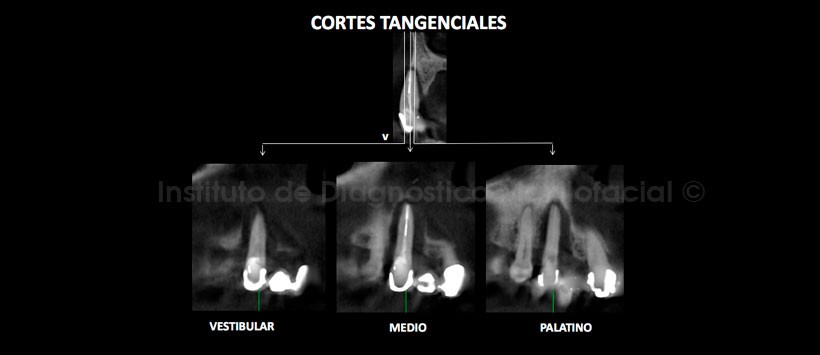

A la evaluación de la tomografía volumétrica (CBCT) en cortes axiales (Figura 2), transaxiales (Figura 3) y tangenciales (Figura 4), se evidencia reabsorción moderada del reborde dento-alveolar de la pieza 13 con presencia de defecto óseo peri-radicular de pieza dentaria 13 que ocasiona la pérdida de la tabla ósea vestibular.